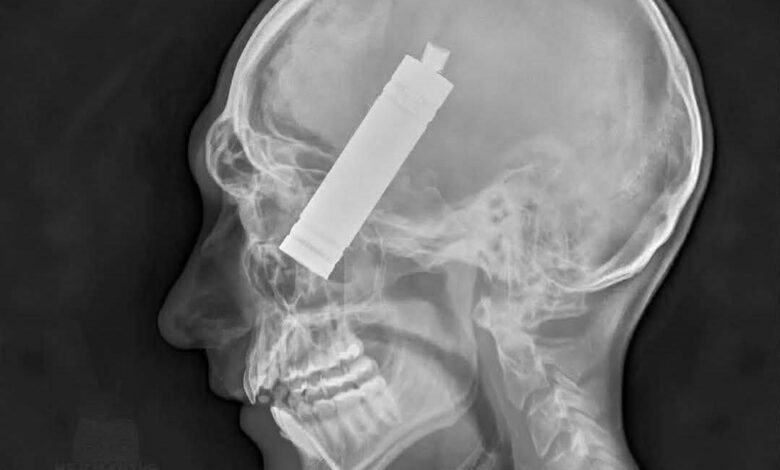

الضحية رجل يبلغ من العمر 38 عامًا من ولاية فلوريدا الأمريكية، كان يستخدم جهاز الفيب بشكل طبيعي، قبل أن تنفجر بطارية الليثيوم داخل الجهاز بشكل مفاجئ أثناء وجوده في فمه، وهو ما تسبب في اختراق جزء من الجهاز لوجهه وجمجمته، محدثًا إصابة قاتلة مباشرة في الرأس.